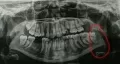

Сегодня ходил к стоматологу, т.к. зуб мудрости начал прорезываться и покрылся капюшоном. В итоге, опухло прямо за ним и перешло на жевательную мышцу.

Мне срезали этот капюшон полтора часа назад, ничего не болело, рот было чуть трудно открывать, а сейчас еле-еле могу открыть, очень больно глотать. Собирался поесть, но сейчас понимаю, что не смогу.